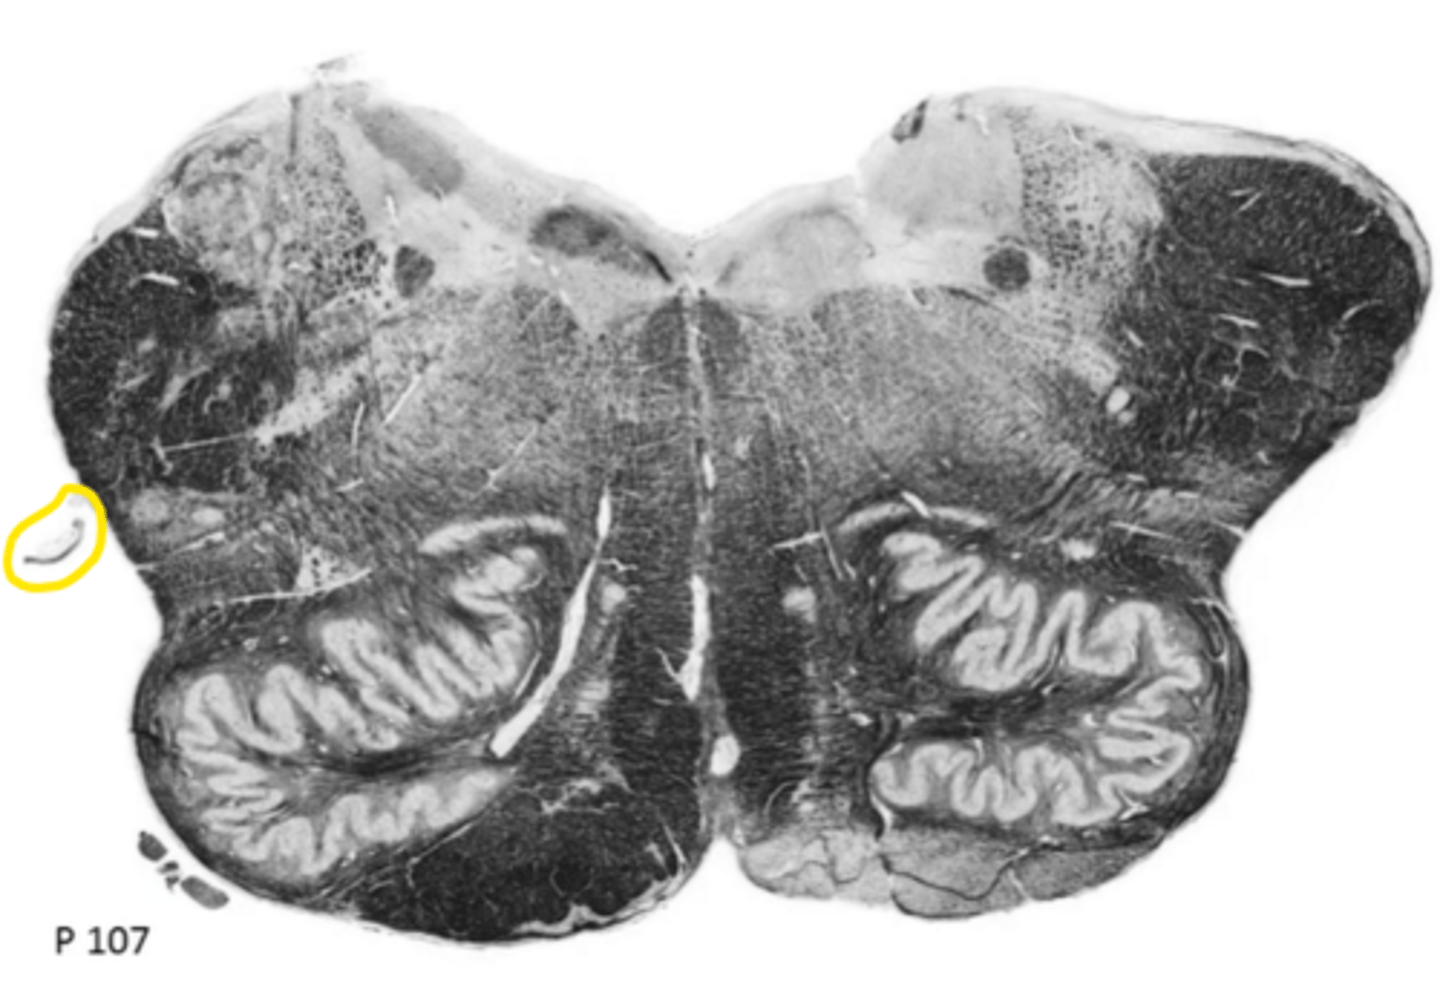

closed medulla

ID the brainstem level